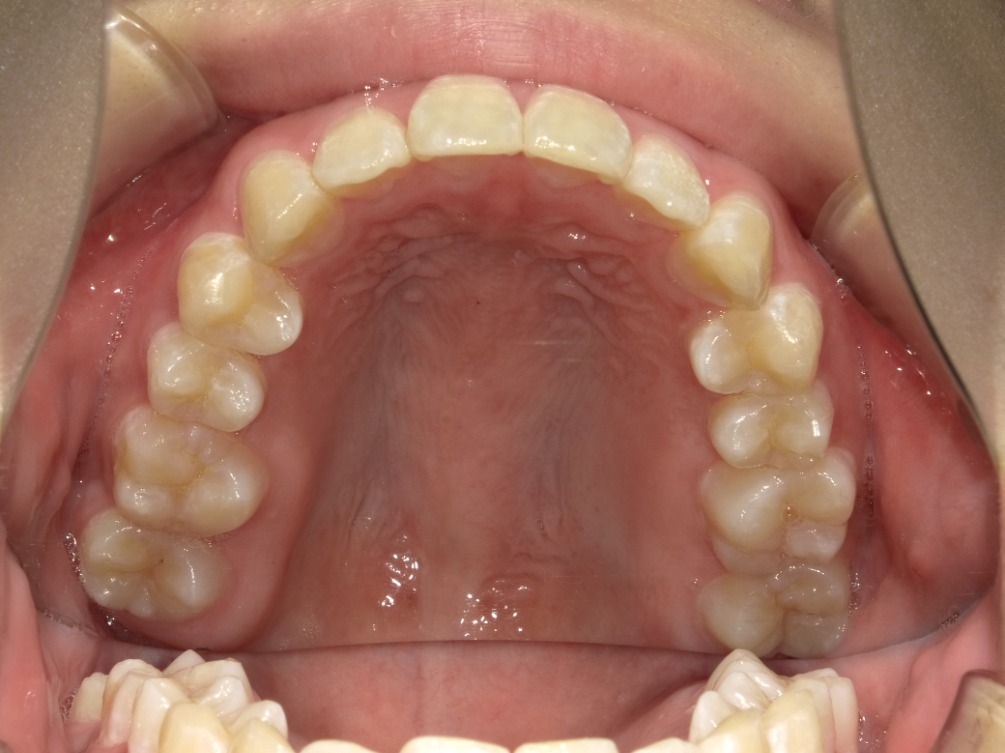

• BEFORE

症例集 インビザライン 上顎

矢印

AFTER

上顎